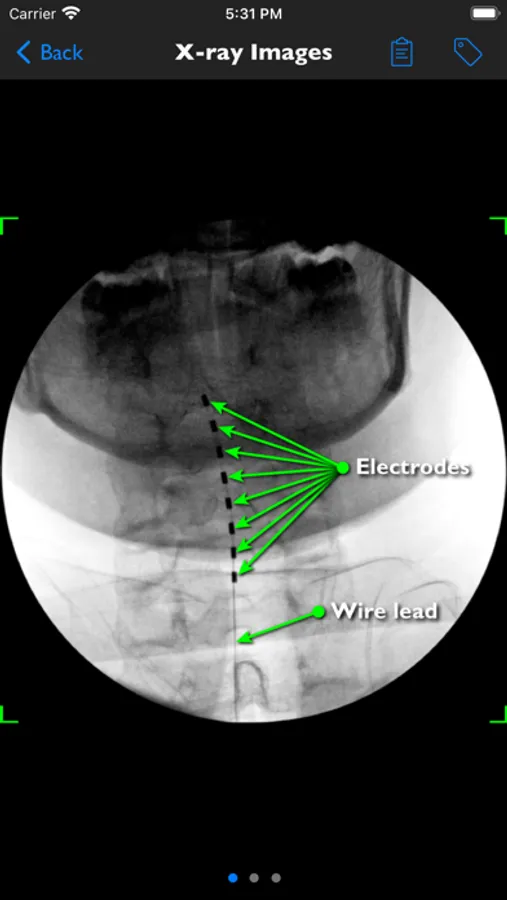

iSpinePainManagement provides accurate spine pain management goal & technique visualizations for informed consent and education. Medical imaging shows real world examples and educational notes cover the indications, alternatives, expectations and complications.